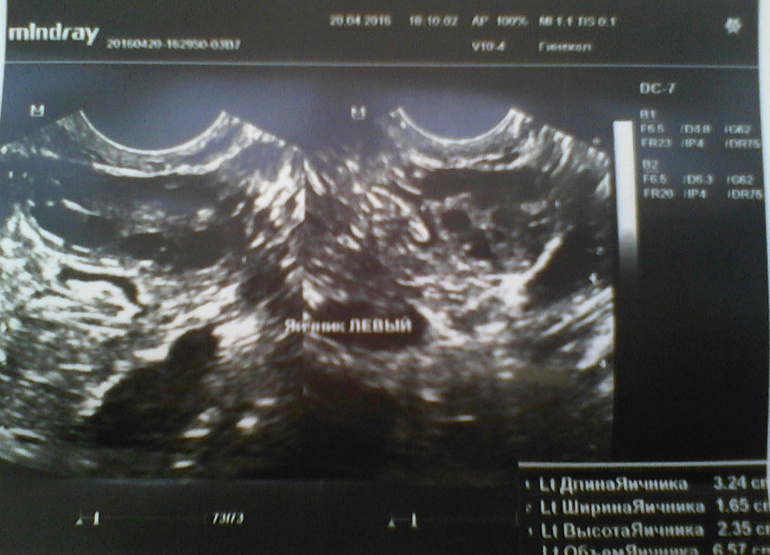

Сегодня 15ДЦ, решила сходить на УЗИ, проверить как-там мои фолики в этом цикле и опять ..........ДФ нет!!!!! Уже третий цикл подряд я без О!!!Получается, что этот цикл пролётный, в следующем только сдам гормоны и только потом, на 3 цикл мне уже хоть что-нибудь назначат(((((К слову БТ высокая в первой фазе, средняя 36,8!Последние два цикла были 20 и 25 дней....посмотрим, что будет на этот раз!

Результаты УЗИ прилагаю!